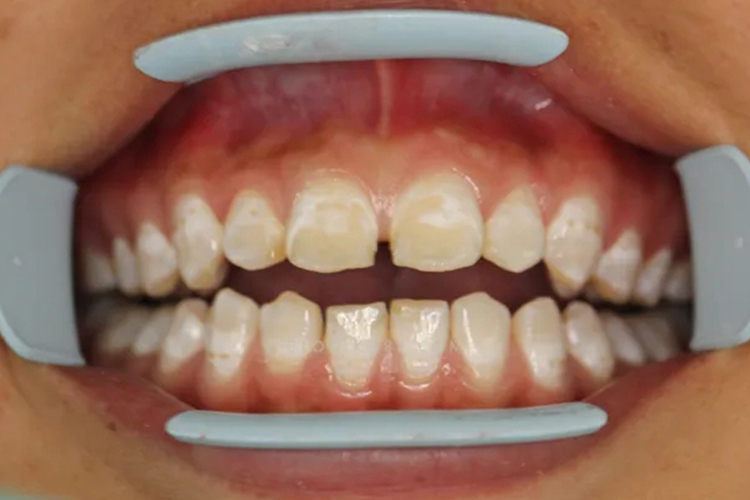

牙齿上有一条一条的黄线通常是由氟牙症、龋齿、四环素牙导致,表现为分布不均的黄色线条。

牙齿上有一条一条的黄线通常是由氟牙症、龋齿、四环素牙导致,具体症状如下:

四环素牙

四环素牙初期呈黄色,在阳光下呈现明亮的黄色荧光,逐渐由黄色变成棕褐色,可伴随一条条的黄线。

是四环素族药物引起的牙着色改变。在牙发育矿化期服用四环素族药物,药物被结合到牙体组织内,药物本身或者其降解产物的颜色使牙着色诱发。

已形成的四环素牙,可通过漂白、光固化复合树脂修复、贴面修复、烤瓷冠修复等方法治疗。